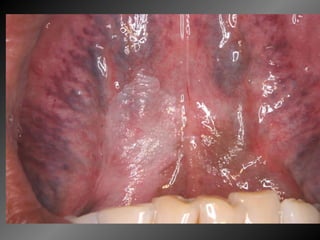

Manifestações Bucais da AIDS (Patton  et al .,2002) Apesar das diferenças em métodos e limitações de alguns estudos, as lesões que parecem mais prevalentes no paciente HIV positivo são a  candidíase pseudomembranosa e a leucoplasia pilosa

Manifestações Bucais da AIDS (Shiboski  et al .,2001) O padrão de ocorrência de lesões associadas com o HIV parece diferir entre crianças e adultos. As lesões mais comuns nas crianças são a  candidíase  (maior prevalência que em adultos) e o  aumento de volume parotídeo , enquanto a leucoplasia pilosa raramente é verificada

Manifestações Bucais da AIDS Poucos estudos abordam a questão da manifestações bucais na AIDS na adolescência Candidíase 6% (+ comum) Leucoplasia pilosa <1% Nenhum caso de aumento parotídeo Lesões bucais associadas com presença de mais de 5.000 cópias virais/ml (Shiboski  et al .,2001)

Manifestações Bucais da AIDS 56,4%  das manifestações bucais de origem fúngica (candidíases pseudomembranosa , eritematosa, hiperplásica e queilite angular) 21%  de manifestações bacterianas (gengivite, GUNA e PUNA) 9,7%  manifestações virais (herpes, leucoplasia pilosa, zoster, molusco contagioso) 10,5%  outras (aftas, pigmerntação por AZT, eritema gengival linear) 2,4%  neoplasias (sarcoma de Kaposi e Linfoma não Hodgkin

Manifestações Bucais daAIDS (Patton et al .,2002) Apesar das diferenças em métodos e limitações de alguns estudos, as lesões que parecem mais prevalentes no paciente HIV positivo são a candidíase pseudomembranosa e a leucoplasia pilosa

Manifestações Bucais daAIDS (Shiboski et al .,2001) O padrão de ocorrência de lesões associadas com o HIV parece diferir entre crianças e adultos. As lesões mais comuns nas crianças são a candidíase (maior prevalência que em adultos) e o aumento de volume parotídeo , enquanto a leucoplasia pilosa raramente é verificada

Manifestações Bucais daAIDS Poucos estudos abordam a questão da manifestações bucais na AIDS na adolescência Candidíase 6% (+ comum) Leucoplasia pilosa <1% Nenhum caso de aumento parotídeo Lesões bucais associadas com presença de mais de 5.000 cópias virais/ml (Shiboski et al .,2001)

Manifestações Bucais daAIDS 56,4% das manifestações bucais de origem fúngica (candidíases pseudomembranosa , eritematosa, hiperplásica e queilite angular) 21% de manifestações bacterianas (gengivite, GUNA e PUNA) 9,7% manifestações virais (herpes, leucoplasia pilosa, zoster, molusco contagioso) 10,5% outras (aftas, pigmerntação por AZT, eritema gengival linear) 2,4% neoplasias (sarcoma de Kaposi e Linfoma não Hodgkin